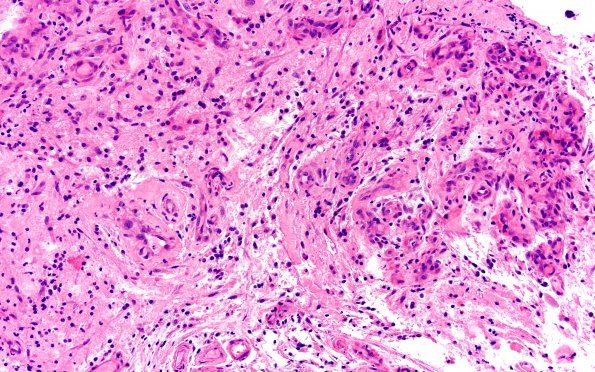

15B5,6 Numerous clusters of microvessels are shown, a number with slight collagenous thickening (H&E).